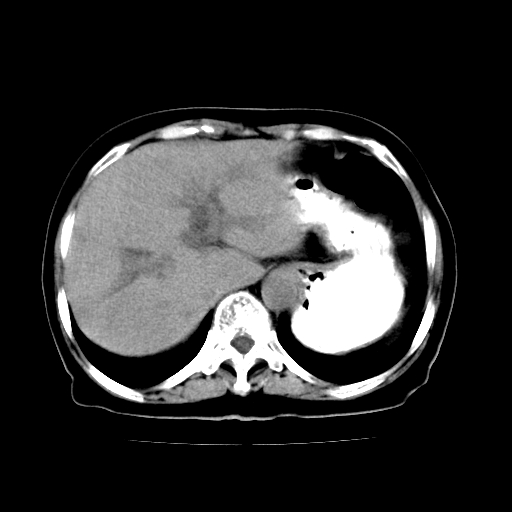

女,74岁,上腹部不适、腹胀两月余,黄染四天。请大家看看肿块周围血管情况。

肝内外胆管增粗,梗阻点位于胰头部,胰头增大,轻度不均性强化(较正常胰腺强化低,胰体尾呈退化';羽毛状';),孝虑为胰头ca.

肝内外胆管和胰管扩张,胆囊明显增大,胰头外形增大,无强化,考虑:胰头癌伴肝内外胆管、胆囊扩张积液。

肝内外胆管增粗,梗阻点位于胰头部,胰头增大不均性明显强化,胰体尾部萎缩,胰管显影,虑为胰头ca.

肝内外胆管及胆囊扩张,胰管扩张,但“双管征”不明显,胆总管下段内见软组织有强化影,肠系膜上静脉推移不是很明显,考虑胆总管下段癌可能大。